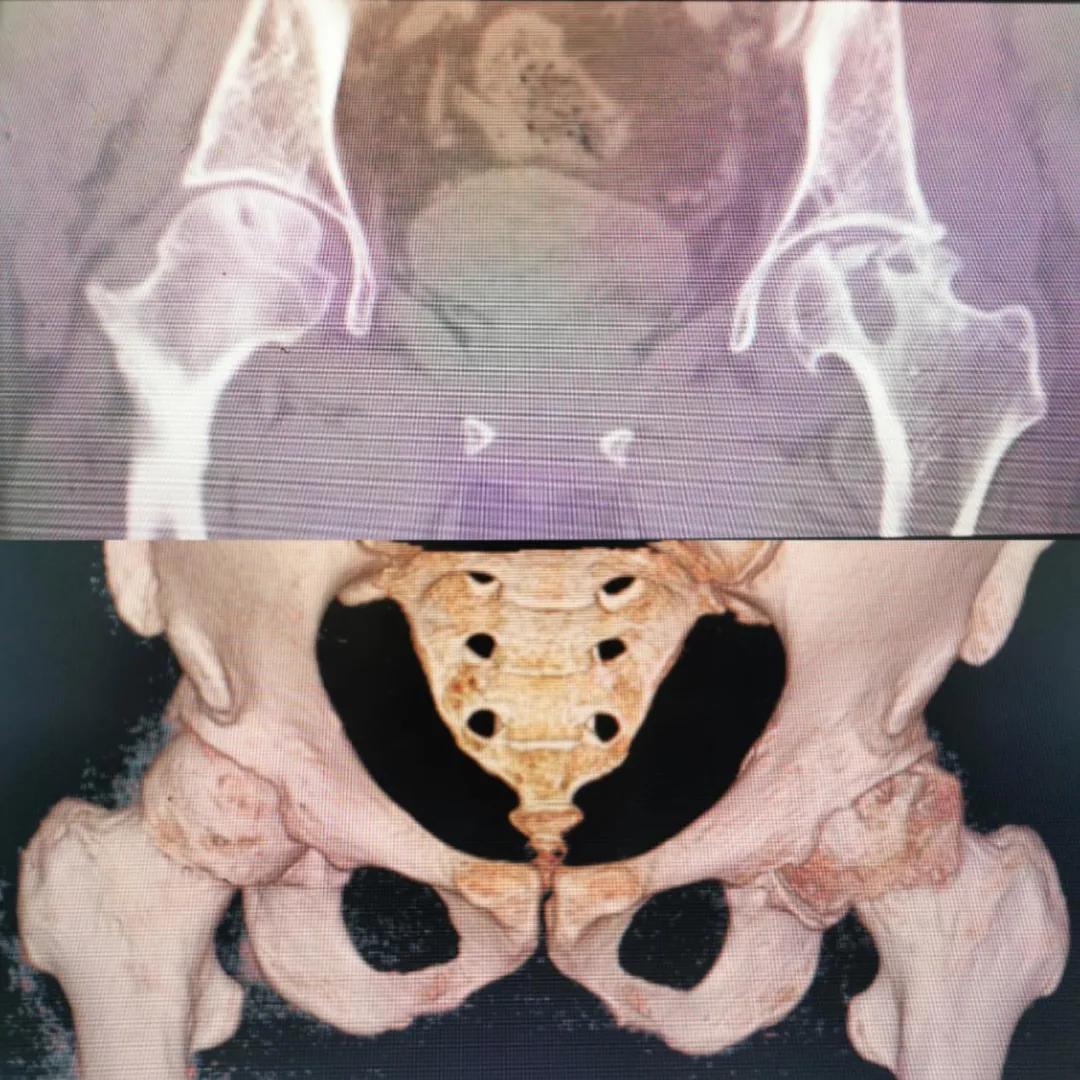

入院急查血結(jié)果提示炎癥反應(yīng),感染較重,凝血功能及肝功均不同程度損害;髖關(guān)節(jié)磁共振(MRI)檢查提示雙側(cè)股骨頭缺血壞死,繼發(fā)髖關(guān)節(jié)炎,左側(cè)髖周軟組織腫脹。醫(yī)療團(tuán)隊(duì)給出的初步診斷為膿毒血癥、股骨頭缺血性壞死、軟組織感染、皮膚潰瘍及閉孔神經(jīng)損傷。

圖片(圖為患者入院時(shí)髖部CT檢查)

追溯病史,患者訴前不久曾用蜂蜇療法治療股骨頭壞死,每日4次,每次100只蜜蜂蜇雙臀部、髖部,這才導(dǎo)致了病情急劇進(jìn)展。查明了來龍去脈,我院智能微創(chuàng)骨科醫(yī)護(hù)團(tuán)隊(duì)與患者家屬積極溝通病情,給予特殊級(jí)抗生素抗感染以及消腫、止痛等支持治療,同時(shí)對(duì)潰瘍創(chuàng)面進(jìn)行專業(yè)、規(guī)范的清創(chuàng)、換藥處理,保護(hù)創(chuàng)面降低感染程度;護(hù)理上輔助翻身,減少壓力性損傷。